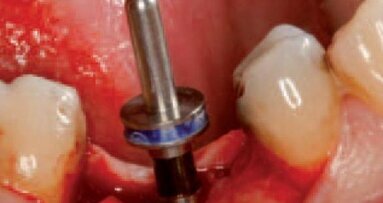

Odsłonięcia struktur kostnych dokonano poprzez wykonanie nacięcia poprowadzonego podniebiennie od szczytu wyrostka bez wykonywania horyzontalnych cięć odbarczających. Wprowadzony został implant Astra 3,5 mm (AstraTech AB, Szwecja), a powstała od strony przedsionkowej dehiscencja i fenestracja została pokryta materiałem BioOss (Geistlich Pharma, Szwajcaria) oraz membraną resorbowalną BioGide. Rana została zaszyta szwami pojedynczymi.

Zaplanowano 16-tygodniowy okres gojenia. Na czas gojenia wykonano odbudowę tymczasową, wykorzystując koronę z utraconego filaru.

Ryciny pokazują sytuację po odsłonięciu implantu i 2-tygodniowym okresie gojenia z wykorzystaniem śruby gojącej. Na implancie wykonano koronę tymczasową z kompozytu, co umożliwiło jej łatwą modyfikację w gabinecie. Stwierdzono prawie 2 mm recesję dziąsła oraz brak brodawek dziąsłowych przy zębach sąsiednich.